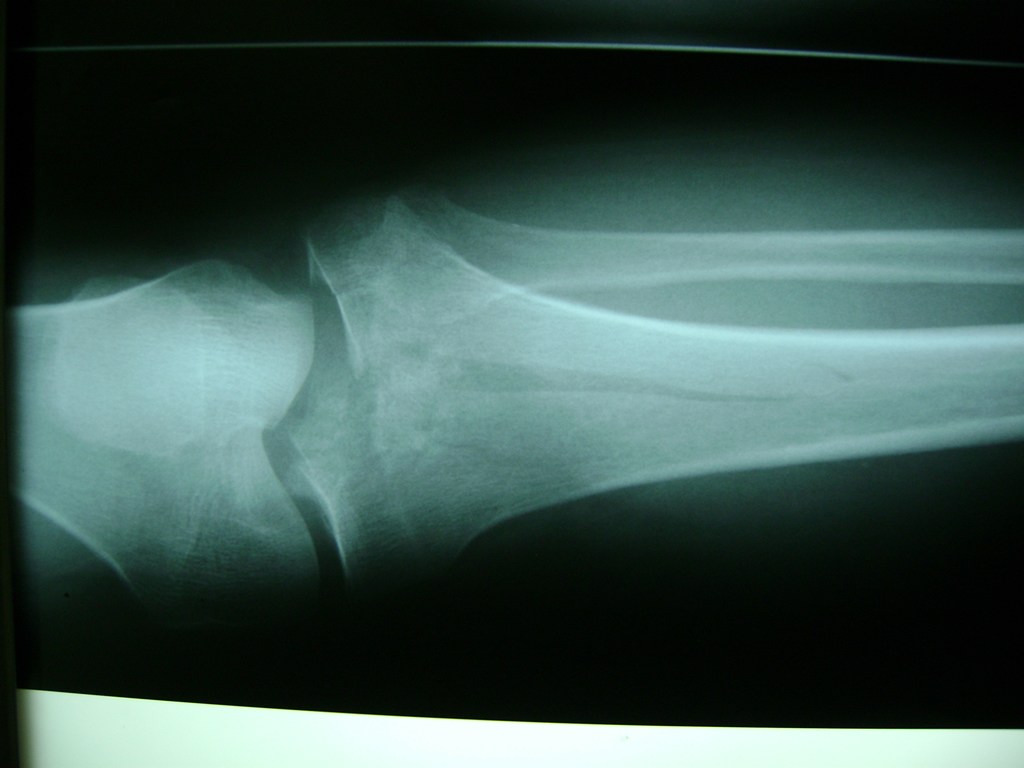

Fémur - Rodilla